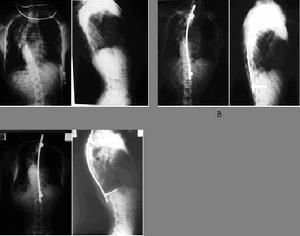

(1)X線片檢查最為重要,一般藉助X線片就可以區別側凸的原因、分類以及彎度、部位、鏇轉、骨齡、代償度等。

常規的X線片應包括站立位的脊柱全長正側位攝片,上端包括下頸椎、下端包括雙側腰骶關節和髂骨翼。其他特殊的X線片包括仰臥位側彎位片,牽引位片等,可以評估脊柱側彎的柔韌性。